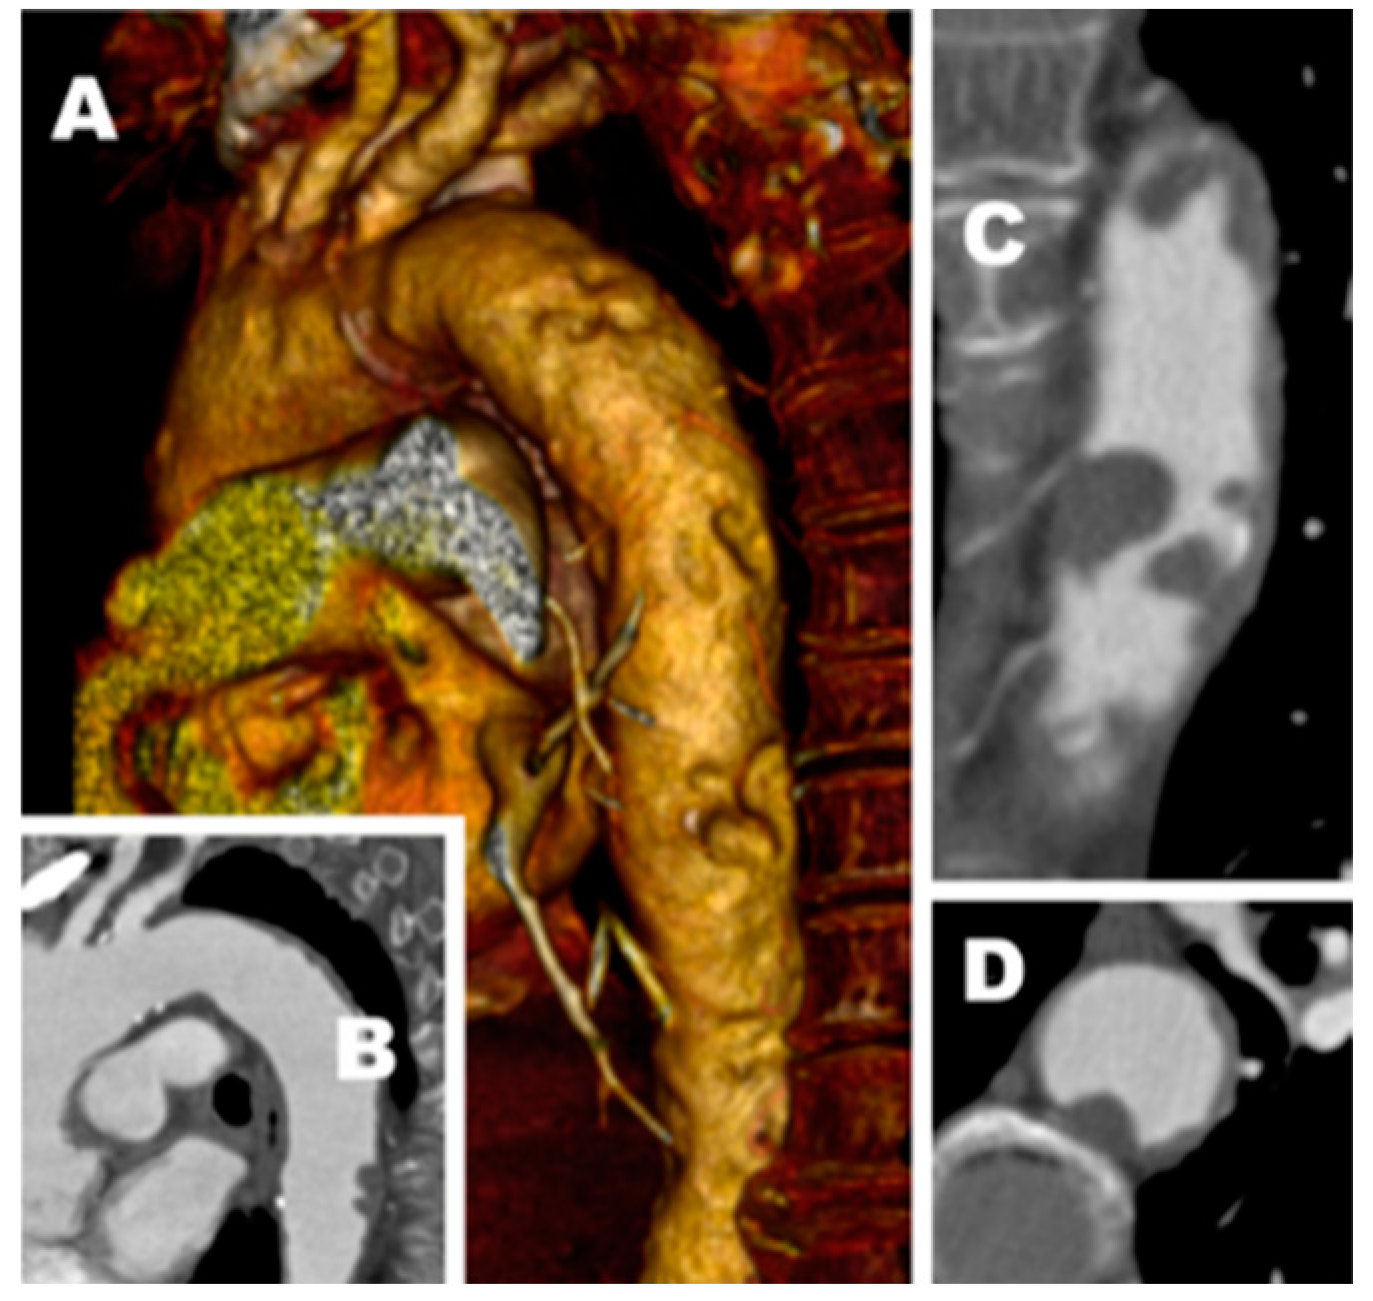

Single-Center Experience with Simultaneous Mural Aortic Thrombosis and Peripheral Obstructive Disease in Pre-COVID-19 and COVID-19 Era

3. Results